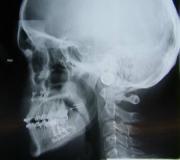

Når du er henvist til Afdeling for Kæbekirurgi, bliver du indkaldt til en forundersøgelse, hvor vi klarlægger dit behandlingsbehov og behandlingsforløb. Du skal også til en konsultation hos en specialtandlæge, hvor du får taget røntgenbilleder og tandaftryk.

Ved første besøg

Du vil blive set af en kæbekirurg og du vil få taget røntgenbilleder og/eller en scanning. Under besøget vil dit ansigt blive målt og oplysningerne tastet ind i et skema. Disse mål samt dine røntgenbilleder og/eller scanning, vil blive brugt på en efterfølgende konference, hvor der bliver lagt en ortodontisk behandlingsplan og en kirurgisk behandlingsplan.